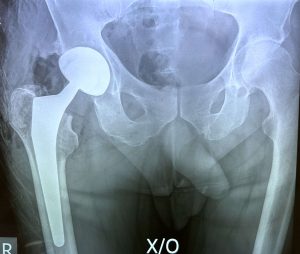

Ακτινολογική απεικόνιση της λεκάνης και των ισχίων στην οποία διακρίνεται η αντικατάσταση της πάσχουσας άρθρωσης με ολική αρθροπλαστική του ισχίου ελάχιστης επεμβατικότητας ALMIS.

Δύο μήνες μετά το χειρουργείο η ποιότητα της βάδισης του ασθενούς έχει βελτιωθεί και δεν αναφέρει καθόλου πόνο. O ασθενής δεν χρειάζεται μπαστούνια πια.